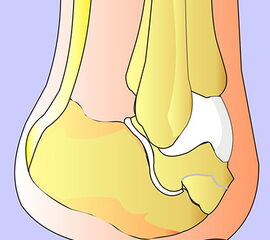

Schema der Amputationsniveaus am Fuß von der Seite.

Grün: empfohlene Amputationslinien.

Rot: nicht empfohlene Amputationslinie.

Abbildung 1

Die Amputationslinien am Fuß, die sich uns bewährt haben, sind in der Abb. 1 schematisch dargestellt.